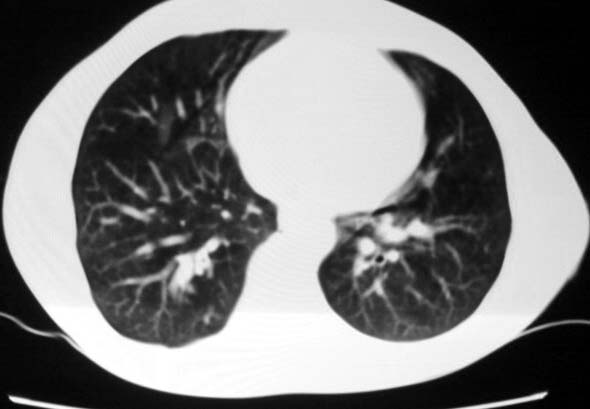

标题: CT5614:外伤病人男,20岁,右上腹痛.余肺野(-)

外伤病人男,20岁,右上腹痛,ct显示:右肺下叶后基地段见斑片状高密度影,密度不均,边界清,考虑1,右肺下叶肺挫伤;2,炎症。

可以肯定的是与外伤无关。肺挫伤是片状渗出影:边缘比中心密度低,呈毛玻璃状,如果是结节状肺挫伤(肺内血肿)应该边缘光滑,不会与后壁胸膜有轻度粘连。此病灶分叶状,周围有卫星灶(纤维条索影及小结结影),考虑结核.